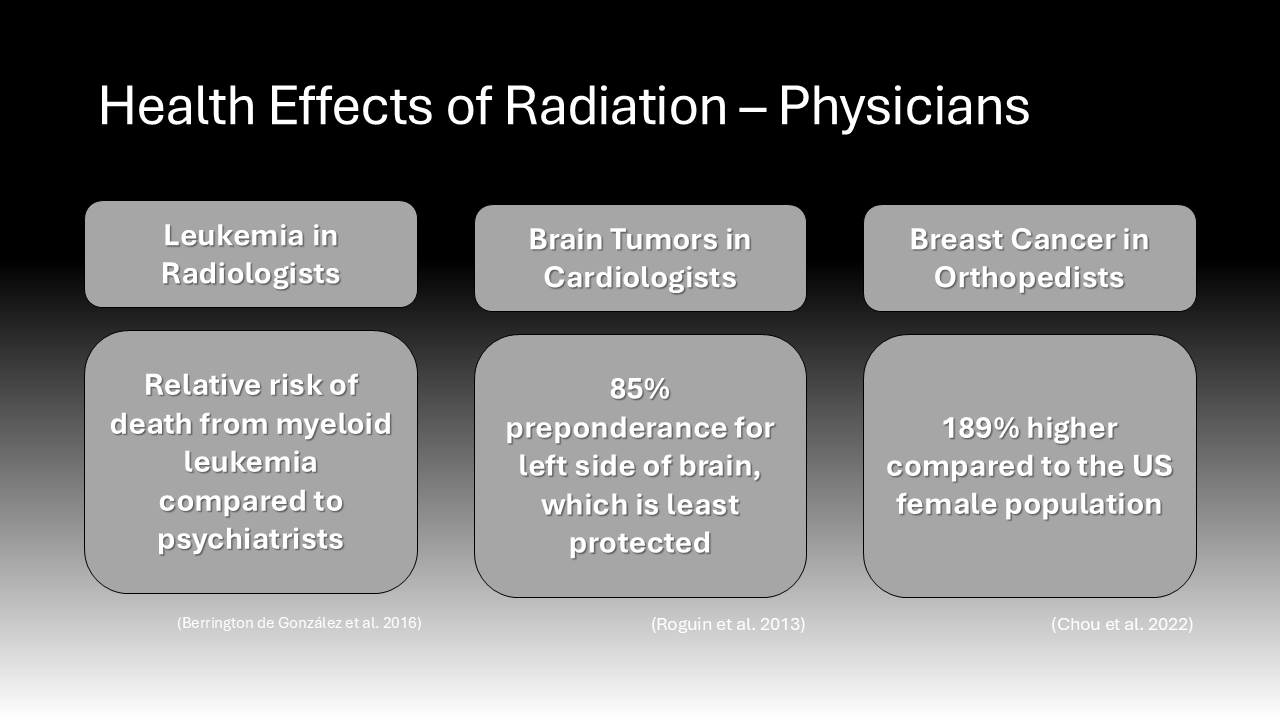

Observed trends of increased specific cancer incidence in physicians of certain specialties renew the community’s concern over the effects of radiation exposure. Clusters of cancer types seem to be correlated with occupational radiation exposure by physicians. For instance, a cohort study comparing 43,000 radiologists to a control group of psychiatrists found that the relative risk of death from myeloid leukemia was 1.43 in the radiologists.11 Another study found that a group of cardiac interventionalists with radiation-associated head and neck tumor subtypes, such as glioblastoma, had a disproportionate number of brain tumors originating on the left side of the brain. Eighty-five percent of the physician’s tumors were left-sided, while in the general population, brain tumors are equally likely to occur on either side of the brain.14 The researchers explained this preponderance of left-sided brain tumors by the fact that the left side of the head typically experiences the highest burden of radiation as it is least protected by the typical shields.14 This supports the conclusion that shared radiation exposure during procedures increases cancer risk in this group. Furthermore, numerous studies demonstrate a higher incidence of breast cancer among female orthopedic surgeons compared to the general population and other surgeons not exposed to radiation.10 A recent study contacting 1290 female orthopedic surgeons determined that the prevalence of breast cancer was 189% higher among this group compared to the US female population, even after adjusting for age and race.10 While the increased risk for breast cancer in this cohort might be attributable to delaying childbearing, this cohort had many more lifestyle factors that were protective against breast cancer, such as normal weight.10 This suggests that their occupational exposure to radiation in surgery was significant enough to increase their risk of breast cancer. In sum, there is a considerable amount of data suggesting that physicians exposed to radiation from the use of intraoperative imaging technology are at an increased risk of developing several types of cancer and new evidence continues to emerge.